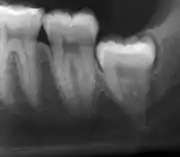

The diagnosis of impaction can be made clinically if enough of the wisdom tooth is visible to determine its angulation, depth, and if the patient is old enough that further eruption or uprighting is unlikely. Wisdom teeth continue to move to the age of 25 years old due to eruption, and then continue some later movement owing to periodontal disease.[18]

If the tooth cannot be assessed with clinical exam alone, the diagnosis is made using either a panoramic radiograph or cone-beam CT. Where unerupted wisdom teeth still have eruption potential several predictors are used to determine the chance of the teeth becoming impacted. The ratio of space between the tooth crown length and the amount of space available, the angle of the teeth compared to the other teeth are the two most commonly used predictors, with the space ratio being the most accurate. Despite the capacity for movement into early adulthood, the likelihood that the tooth will become impacted can be predicted when the ratio of space available to the length of the crown of the tooth is under 1.[5]: 141